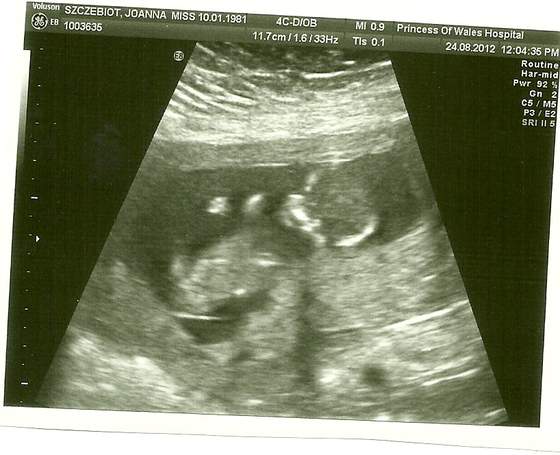

Zobacz załącznik 506927 18+2 wg OM